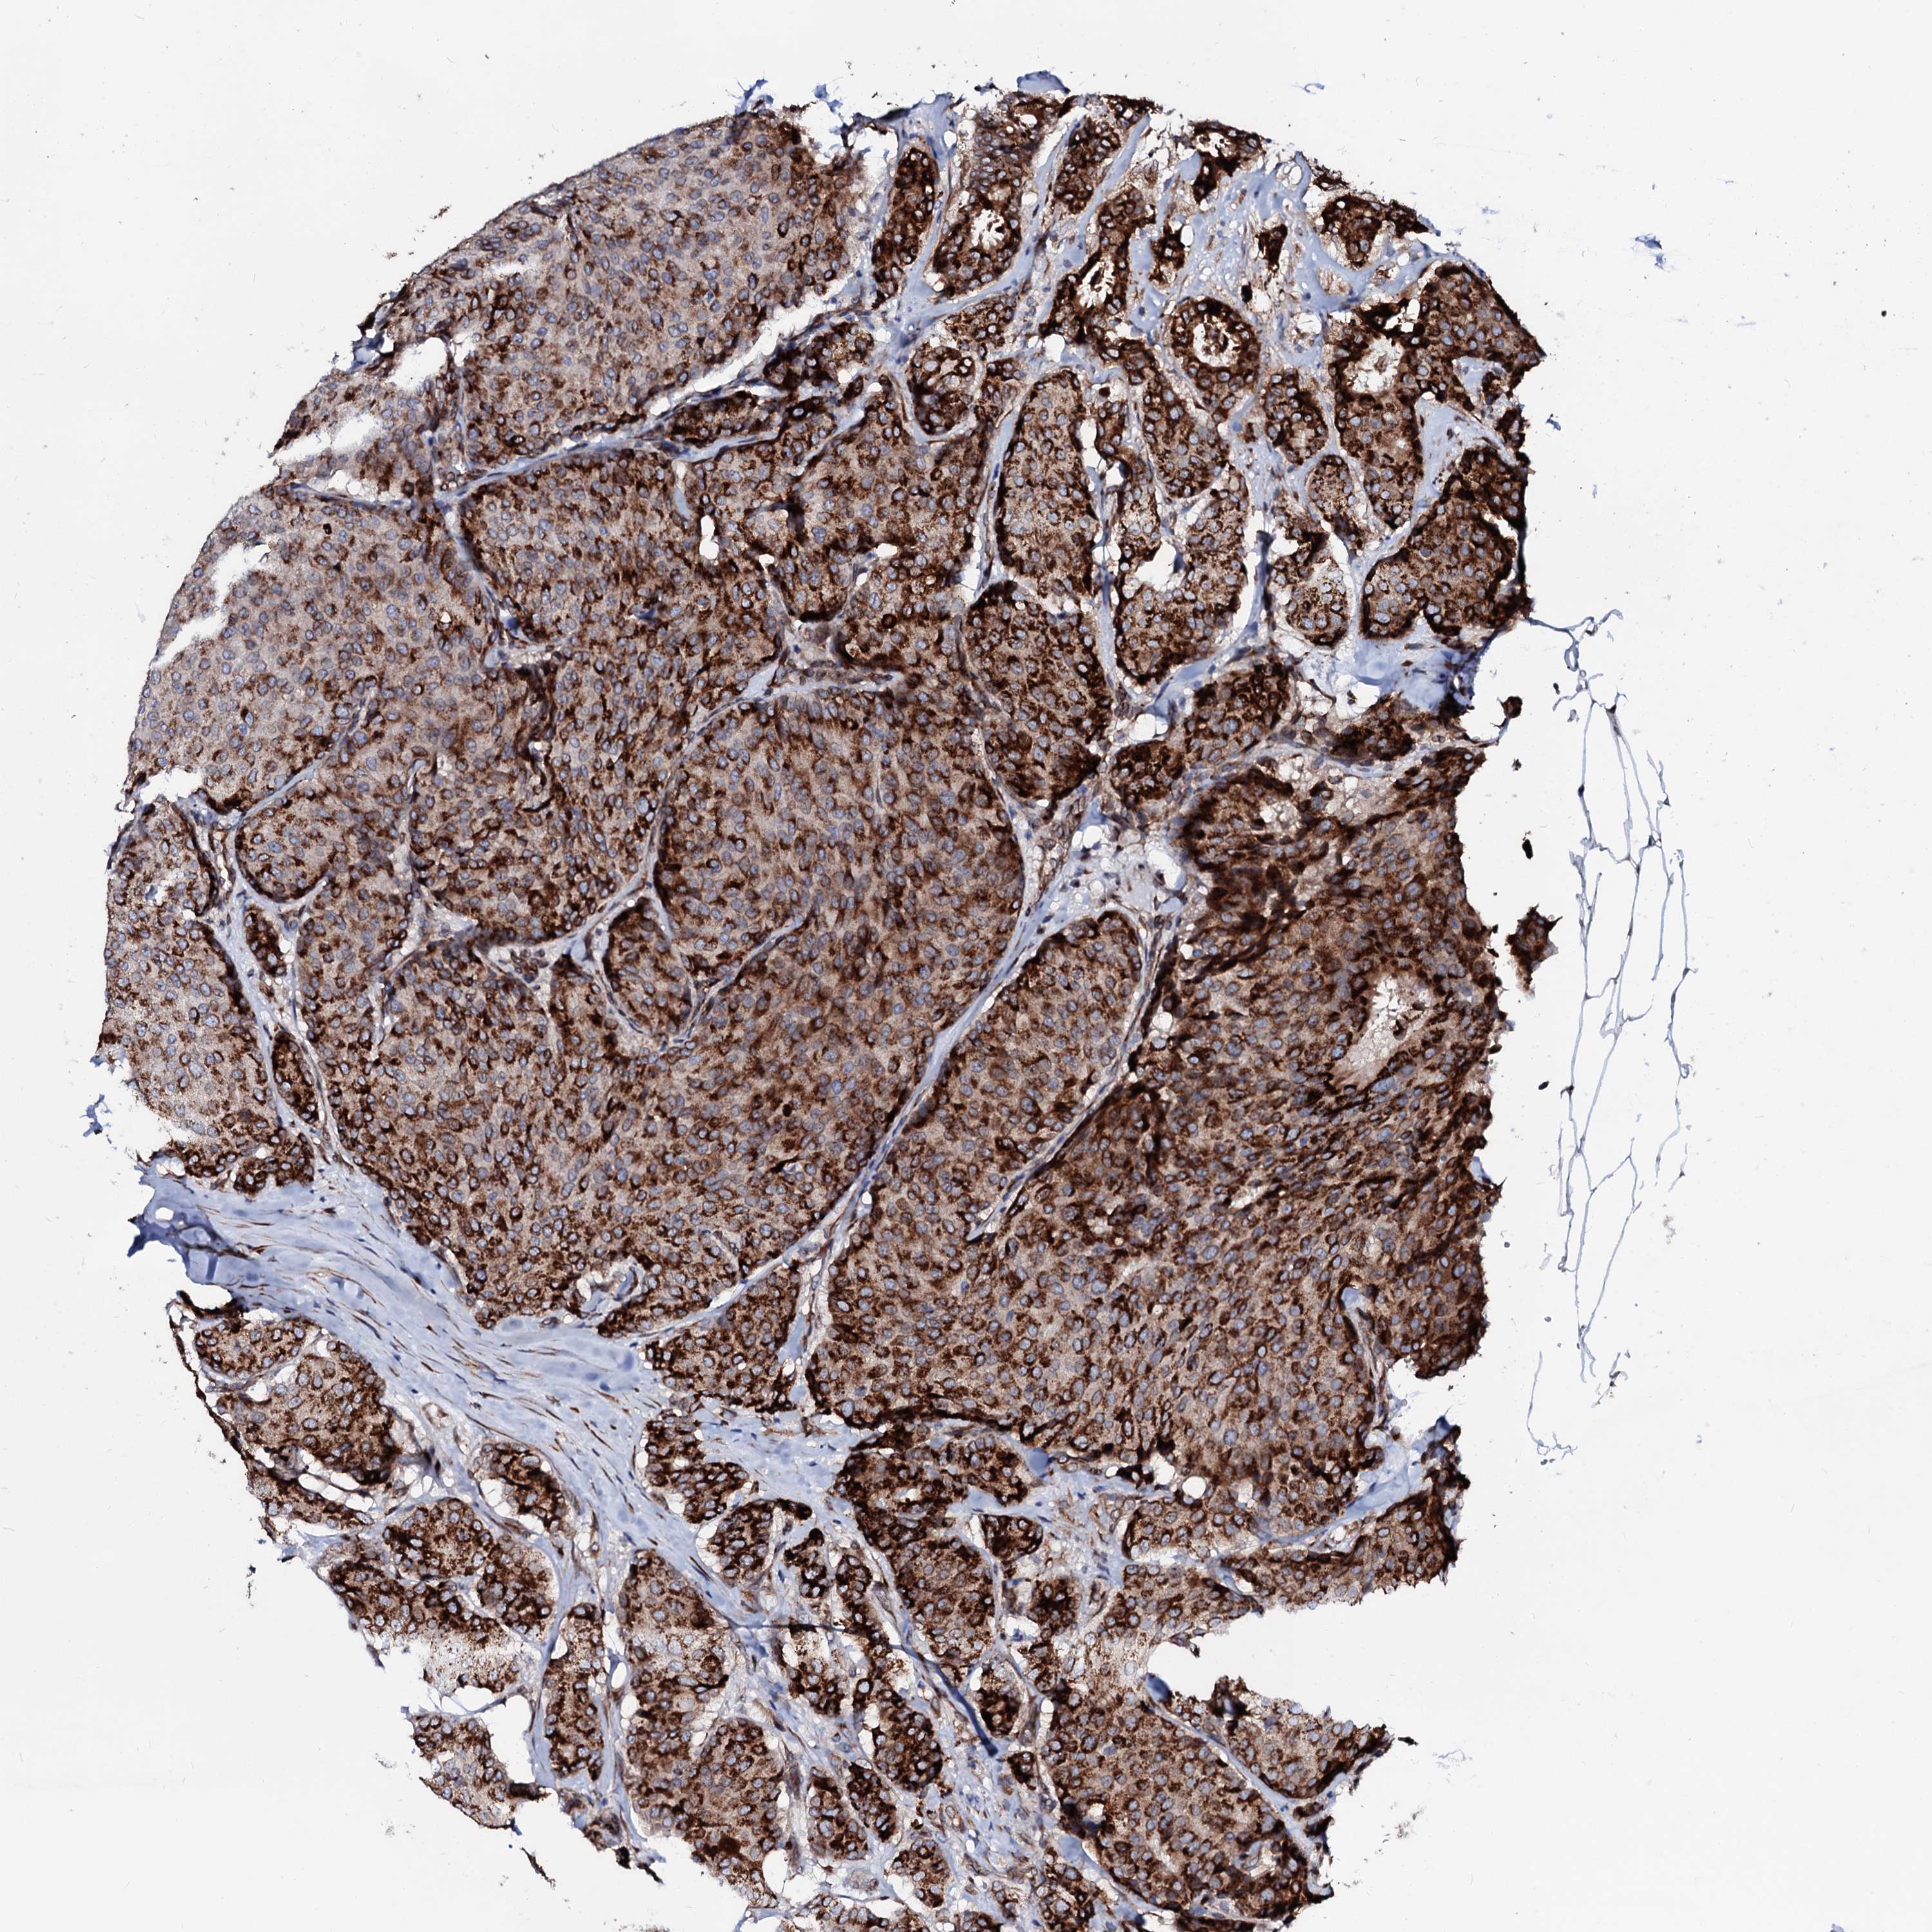

BRCA TCGA BRCA VALIDATION PROTEIN EXPRESSION

ANTIBODIES

AND

VALIDATION